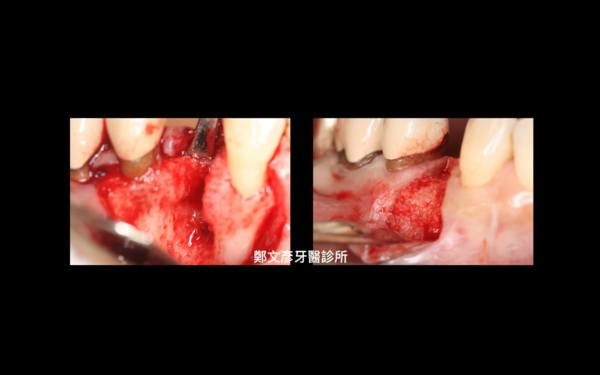

Role of granulation tissue in socket preservation

3. Role of granulation tissue in socket preservation